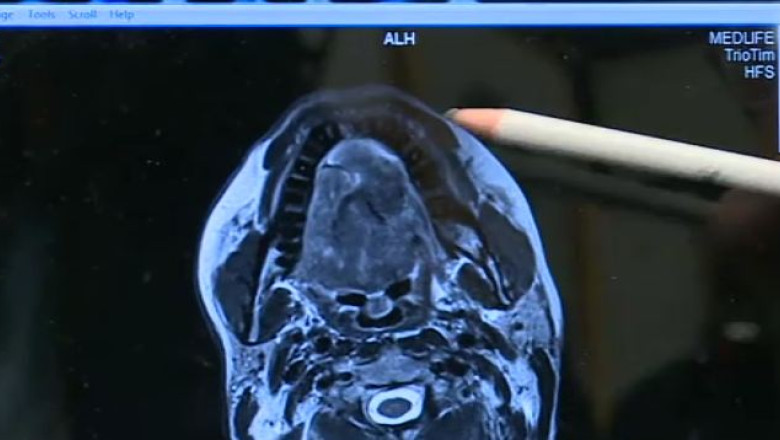

Viaţa bolnavului depindea în totalitate de această intervenţie, întrucât tumoarea i-a afectat în întregime limba, gâtul, dar şi o parte din creier.